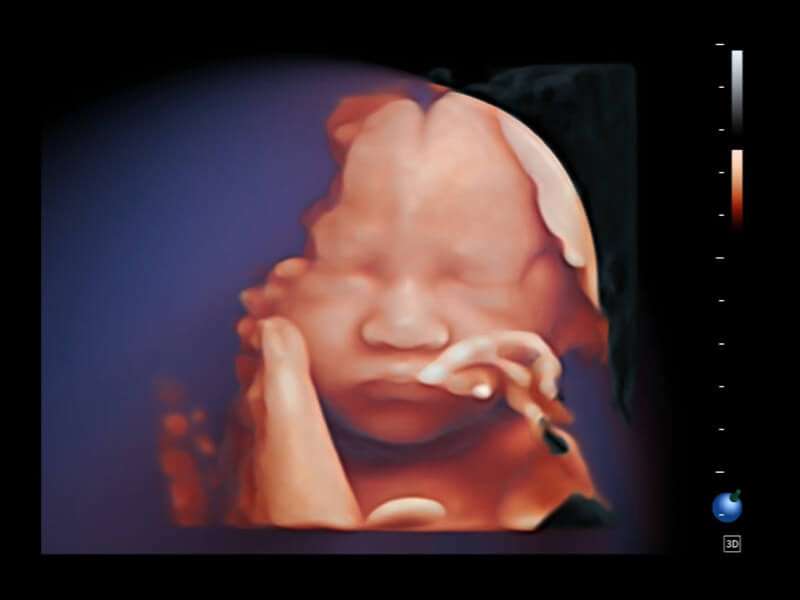

• S-Live Studio liefert eine brillante, realistische Hautvisualisierung in Echtzeit, indem es die Lichtausbreitung auf der Hautoberfläche simuliert und so die Tiefe und Authentizität des dreidimensionalen Bildes bereichert.